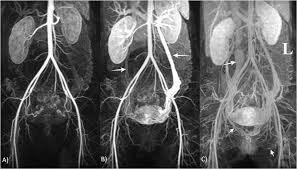

Bunlar ile tanı netlik kazanmazsa, direk toplardamar anjiografisi yapılmaktadır. Hastalığın tedavisinde ise kaçağı ortadan kaldırmak veya azaltmaya yönelik girişimler olmaktadır. Bu yaklaşımların başında özellikle yumurtalık toplardamarlarında geriye kaçışı engellemek için embolizasyon denilen tıkama işlemi yapılmaktadır.

Bu işlem kasıktan veya boyun toplardamarından girilerek yumurtalık toplardamarına ulaşılarak kaçak bölgesi kapatılır. Takip eden süreçte karın içerisindeki, genital ve bacak bölgesindeki varisler gerilemektedir. Bu süreci hızlandırmak için küçük kesiler ile varisler çıkartılabilmekte veya skleroterapi uygulanabilmektedir.